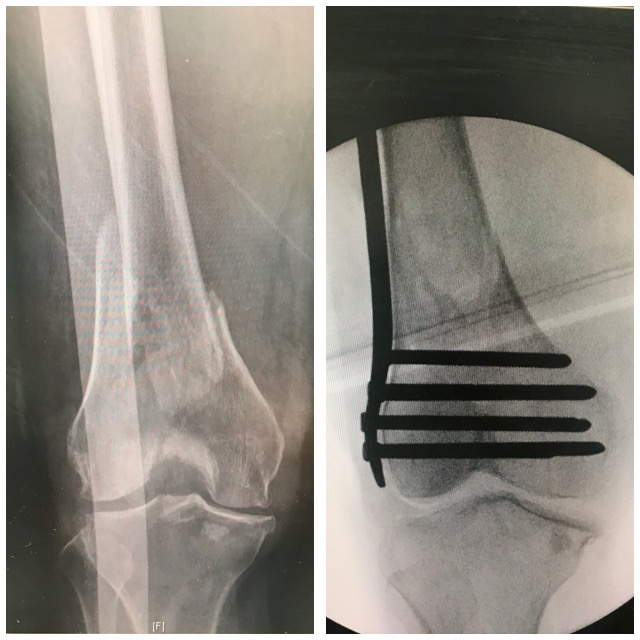

Polven

alueen murtuma

Ennen – jälkeen